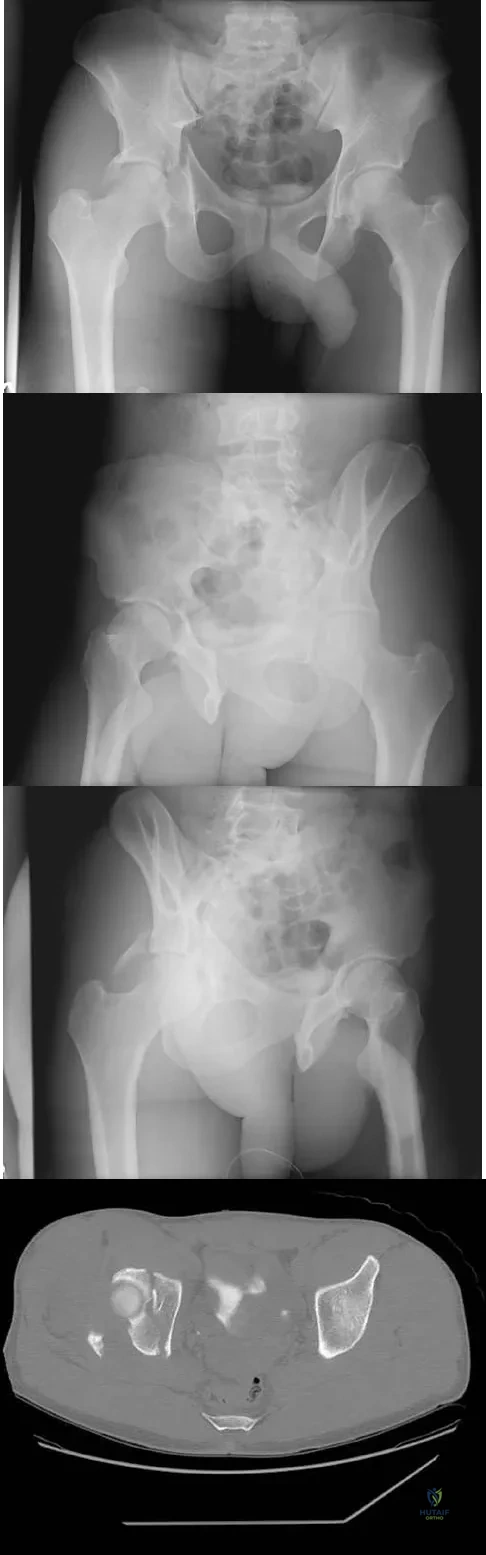

Question 11 High Yield

A 36-year-old woman was injured in a train derailment. She has a significant open depressed skull fracture with active bleeding, a hemopneumothorax, and blood in the left upper quadrant and colic gutter by Focused Assessment with Sonography for Trauma (FAST) examination. Additionally, she has the pelvic injury seen on the CT scans in Figures 18a and 18b. The mortality rate for this patient approaches

Detailed Explanation